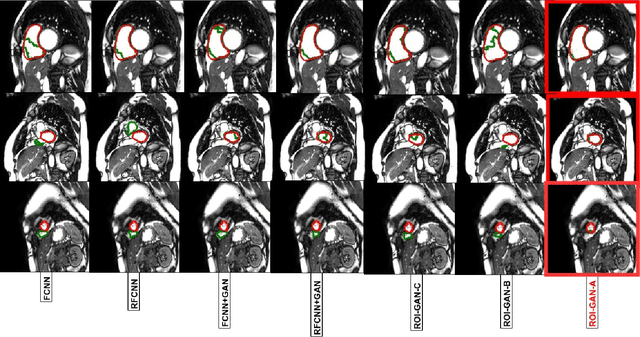

Abstract:The clinical management of several cardiovascular conditions, such as pulmonary hypertension, require the assessment of the right ventricular (RV) function. This work addresses the fully automatic and robust access to one of the key RV biomarkers, its ejection fraction, from the gold standard imaging modality, MRI. The problem becomes the accurate segmentation of the RV blood pool from cine MRI sequences. This work proposes a solution based on Fully Convolutional Neural Networks (FCNN), where our first contribution is the optimal combination of three concepts (the convolution Gated Recurrent Units (GRU), the Generative Adversarial Networks (GAN), and the L1 loss function) that achieves an improvement of 0.05 and 3.49 mm in Dice Index and Hausdorff Distance respectively with respect to the baseline FCNN. This improvement is then doubled by our second contribution, the ROI-GAN, that sets two GANs to cooperate working at two fields of view of the image, its full resolution and the region of interest (ROI). Our rationale here is to better guide the FCNN learning by combining global (full resolution) and local Region Of Interest (ROI) features. The study is conducted in a large in-house dataset of $\sim$ 23.000 segmented MRI slices, and its generality is verified in a publicly available dataset.